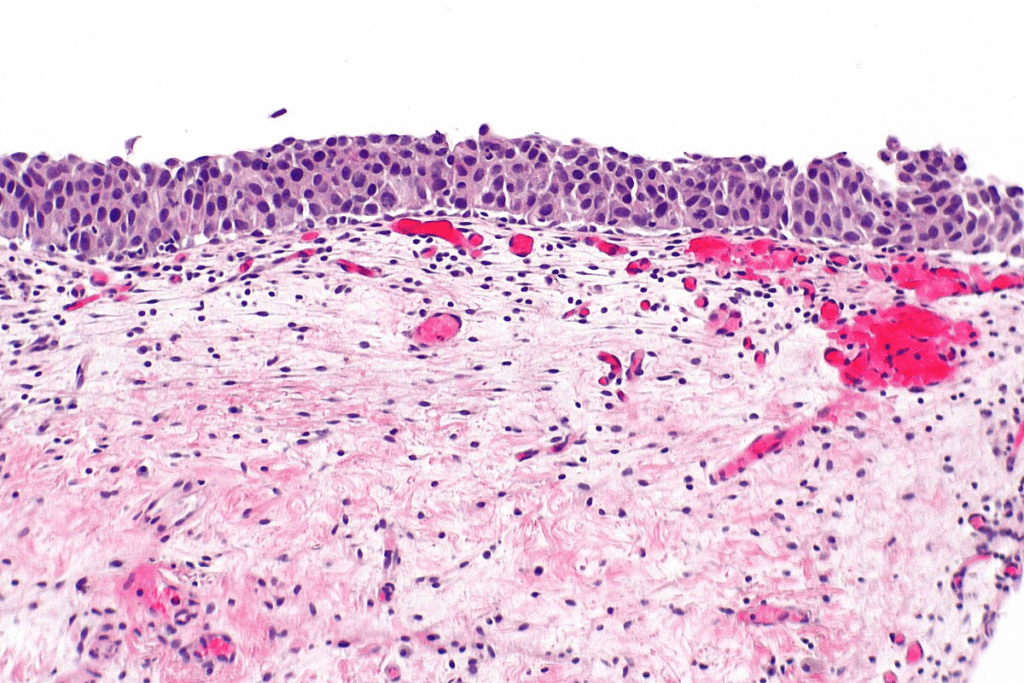

Cellular Changes and Microscopic Appearance

When we look at carcinoma in situ cells under a microscope, they show signs of being cancerous. They have irregular shapes and abnormal nuclei. These signs show they could become cancer, but they’re stuck in their original tissue.

Containment Within Tissue of Origin

A key trait of carcinoma in situ is that it stays in the tissue where it started. The cancer cells haven’t crossed the basement membrane. This thin layer of tissue keeps them from spreading.